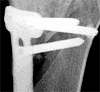

Die aktuellen Röntgenbilder (bitte klicken für grössere Fassungen):

Dasselbe Bild wie oben, Ausschnitt Knie